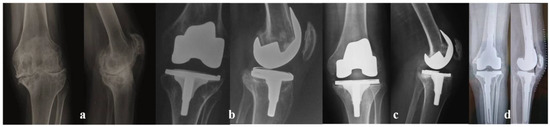

- Innocenti, M.; Matassi, F.; Carulli, C.; Nistri, L.; Civinini, R. Oxidized zirconium femoral component for TKA: A follow-up note of a previous report at a minimum of 10 years. Knee 2014, 21, 858–861. [Google Scholar] [CrossRef]

- Civinini, R.; Matassi, F.; Carulli, C.; Sirleo, L.; Lepri, A.C.; Innocenti, M. Clinical Results of Oxidized Zirconium Femoral Component in TKA. A Review of Long-Term Survival. HSS J. 2017, 13, 32–34. [Google Scholar] [CrossRef]

- Innocenti, M.; Civinini, R.; Carulli, C.; Villano, M.; Linari, S.; Morfini, M. A modular total knee arthroplasty in haemophilic arthropathy. Knee 2007, 14, 264–268. [Google Scholar] [CrossRef]

- Carulli, C.; Innocenti, M.; Linari, S.; Morfini, M.; Castman, G.; Innocenti, M. Joint replacement for the management of haemophilic arthropathy in patients with inhibitors: A long-term experience at a single Haemophilia centre. Haemophilia 2020, 27, e93–e101. [Google Scholar] [CrossRef]